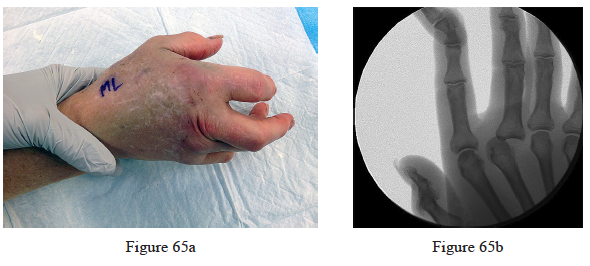

65. Figure 65a is the clinical photograph of a 64-year-old man who crashed while riding his motorcycle. An examination reveals his long-finger metacarpophalangeal (MP) joint is stuck in extension. He cannot passively or actively flex at the MP joint. A hand radiograph is seen in Figure 65b. Which interposed structure is preventing reduction?